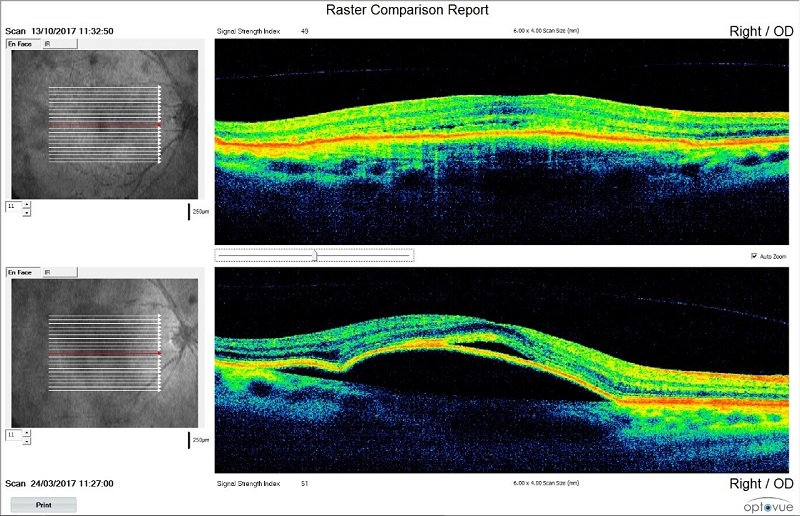

ОСТ преди (долу) и след (горе) 2RT:

Като иновативна терапия при влажната форма приложихме 2RT в комбинация с AntiVEGF. Целта е да изследваме възможността за удължаване интервалите за приложение на antiVEGF медикаменти, както и да се подобри зрителната рехабилитация на тези пациенти. При 80% от пациентите с влажна форма се удължи интервалът за приложение на antiVEGF до 6 месеца. Зрителната острота при 90% се подобри с 1 до 2 реда. Пациентите съобщават за субективно подобрение. Изследването на контрастната чувствителност показва един ред подобрение в 98% от случаите.